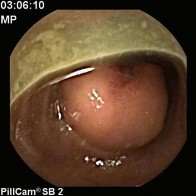

Hình 1.15. U mỡ ác tính ruột non, ảnh chụp từ viên camera nội soi [98]

Ruột non: Tác giả Mohammad Amx (Mỹ) là người đầu tiên thông báo trường hợp u mỡ ác tính của ruột non (1957), khối u này gây tắc ruột do lồng ruột non trên một đoạn 15 cm [95], đây là một trong những biến chứng do u gây ra như tắc ruột, xoắn ruột, chảy máu [84, 96]. Một trong những biến chứng hiếm gặp khác mà tác giả Hasashi (Nhật Bản) và cộng sự đã mô tả là thủng ruột gây viêm phúc mạc do u mỡ ác tính gây ra, đây là một trong hai trường hợp trong y văn mà chúng tôi tìm thấy cùng với bài viết của tác giả người Ba Lan đăng năm 1984 [97]. Chẩn đoán trước mổ bằng lâm sàng thường khó khăn, nhờ có chụp cắt lớp hoặc viên camera nội soi mới cho gợi ý chẩn đoán [98].